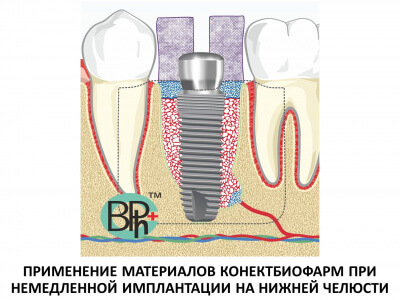

![IMG_2280[1]](http://www.bioimplantat.ru/wp-content/uploads/IMG_22801.jpg) Чем больше соприкосновение биопластического материала с костью и богаче кровоснабжение - тем больше кости Вы получите. Резорбируемые коллагеновые мембраны, такие как Биоматрикс мембрана, в процессе их физиологической реконструкции трансформируются в грубоволокнистую фиброзную ткань, которая формирует дополнительный и надежный барьер между аугментатом и полостью носа.

Чем больше соприкосновение биопластического материала с костью и богаче кровоснабжение - тем больше кости Вы получите. Резорбируемые коллагеновые мембраны, такие как Биоматрикс мембрана, в процессе их физиологической реконструкции трансформируются в грубоволокнистую фиброзную ткань, которая формирует дополнительный и надежный барьер между аугментатом и полостью носа.

Далее мы рекомендуем укладывать Остеоматрикс в виде чипсов. Это остеоиндуктивный материал, который непосредственно участвует в стимуляции процессов костеобразования и в дальнейшем полностью замещается вновь образованной костью (рис 5).

Далее мы рекомендуем укладывать Остеоматрикс в виде чипсов. Это остеоиндуктивный материал, который непосредственно участвует в стимуляции процессов костеобразования и в дальнейшем полностью замещается вновь образованной костью (рис 5).

... с последующим покрытием коллагеновой мембраной Биоматрикс (рис 7).

... с последующим покрытием коллагеновой мембраной Биоматрикс (рис 7).